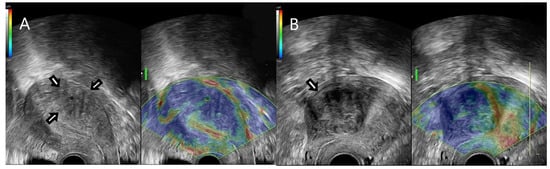

2.2. Ultrasound Examination

2.3. Strain Ratio Elastography Analysis